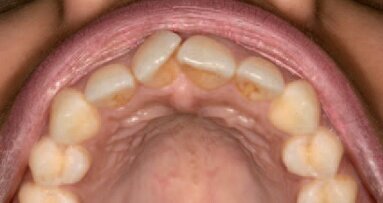

Belfast, Velika Britanija: Prema najnovijem istraživanju naučnika sa Kvins univerziteta u Belfastu (Queen’s University Belfast) aspirin bi mogao da se upotrebi za poništavanje efekata karijesa delujući tako što pojačava delovanje dentalnih stem ćelija na samoreparaciju zubnih tkiva.

Naučnici su u ovom istraživanju kombinovali najnovija znanja iz molekularne biologije i bioinformatike u cilju identifikovanja aspirina kao leka koji ima osobine stimulacije stem ćelija zuba u cilju regeneracije uništenih zubnih tkiva. U toku istraživanja stem ćelije iz zuba su tretirane sa malim dozama aspirina što je dovelo do značajnog pojačanja procesa remineralizacije i ekspresije gena odgovornih za formiranje dentina. Ovo otkriće može da dovede do nove indikacije za primenu aspirina, pored delovanja kod smanjenja upala i bolova.

Vođa istraživačkog tima iz dablina dr Iklas El-karim (D.r Ikhlas el-Karim) izjavio je: “Postoji ogroman potencijal ovog istraživanja da promeni naš pristup lečenju karijesa koji je jedan od najvećih izazova u stomatologiji. Inicijalna laboratorijska istraživanja su pokazala da upotreba aspirina može da predstavlja inovativno rešenje koje bi omogućilop da se zubi sami repariraju.”

“Naš sledeći korak biće razvoj odgovarajućeg sistema koji bi omogućio kliničko testiranje efikasnosti aspirina za primenu u stomatologiji. Ovim novim pristupom mogli bi da smanjimo velike troškove koji se izdvajaju zbog karijesa,” rekao je dr el-Karim.